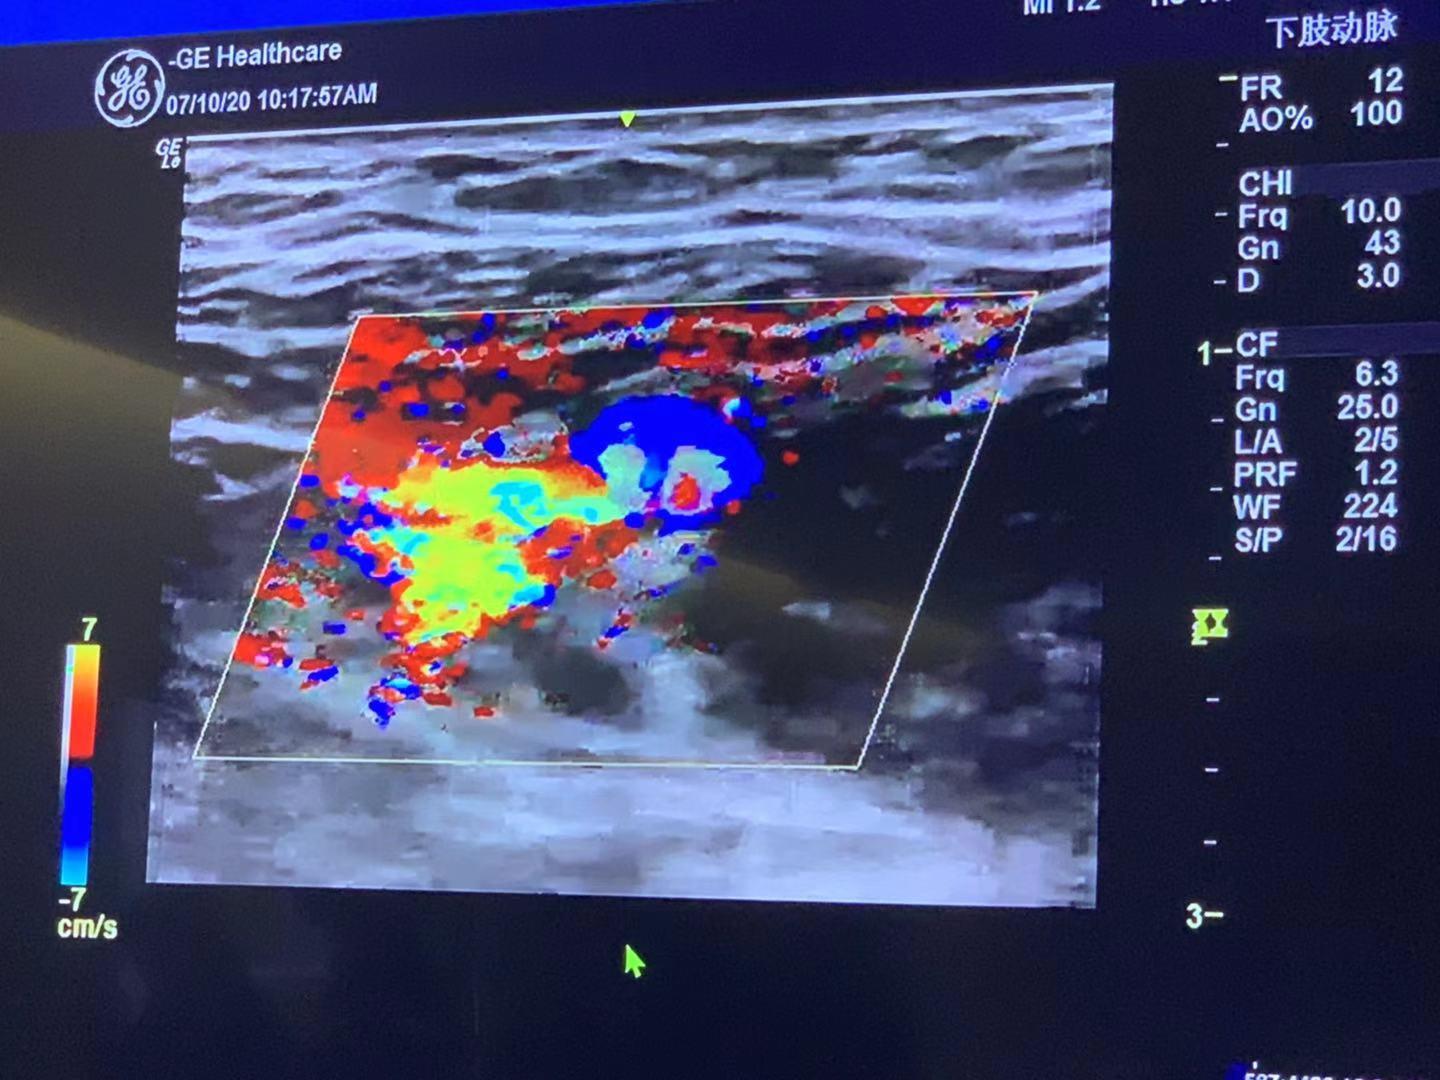

同时,运用人工智能图像识别技术,原本黑白的图像中,现在能通过色彩清晰反映出包括患者的动脉、静脉、血管等准确位置。